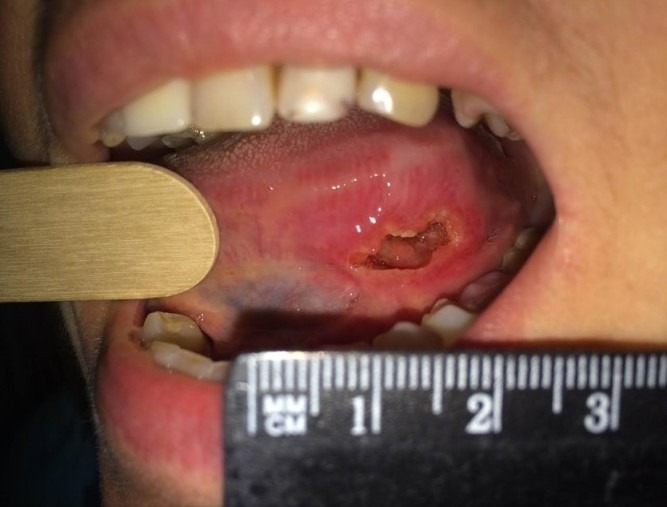

- Язвенная. При этой форме на языке обнаруживается изъязвленная, кровоточащая опухоль.

- долго не заживающие язвы;